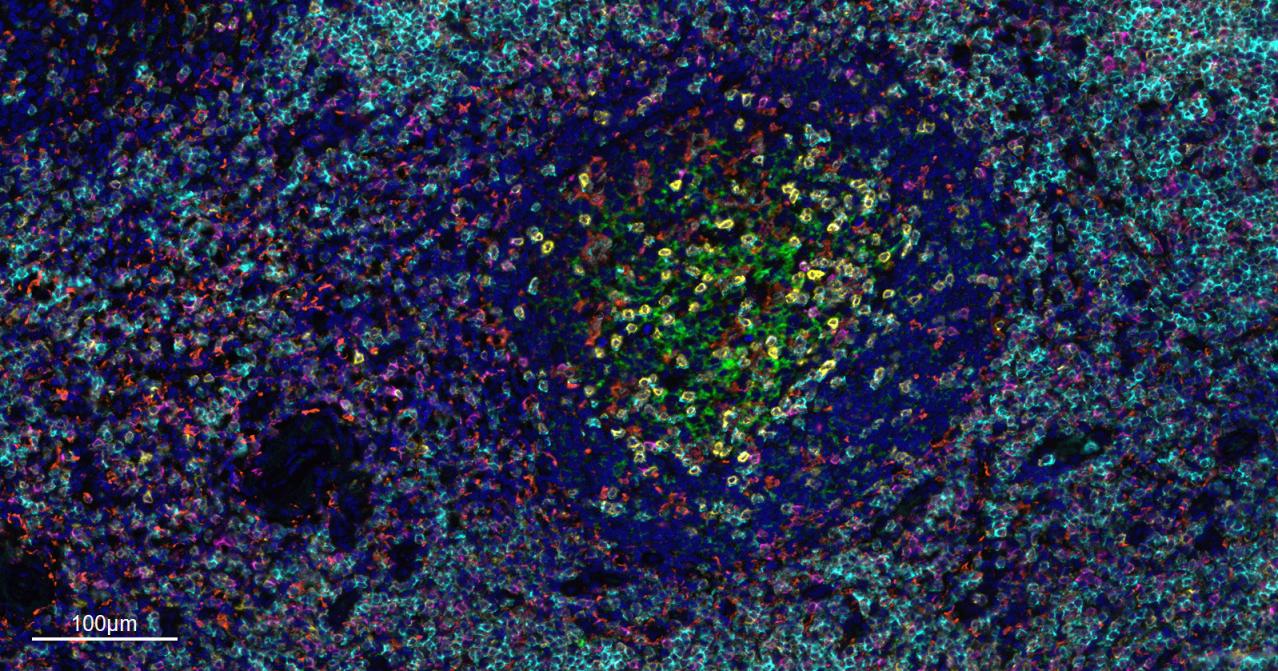

重组兔单抗、mIHC精品抗体

IHC-PHuman, Mouse, Rat1:500-2000

IHC-FHuman, Mouse, Rat1:500-2000

IFHuman, Mouse, Rat1:500-2000